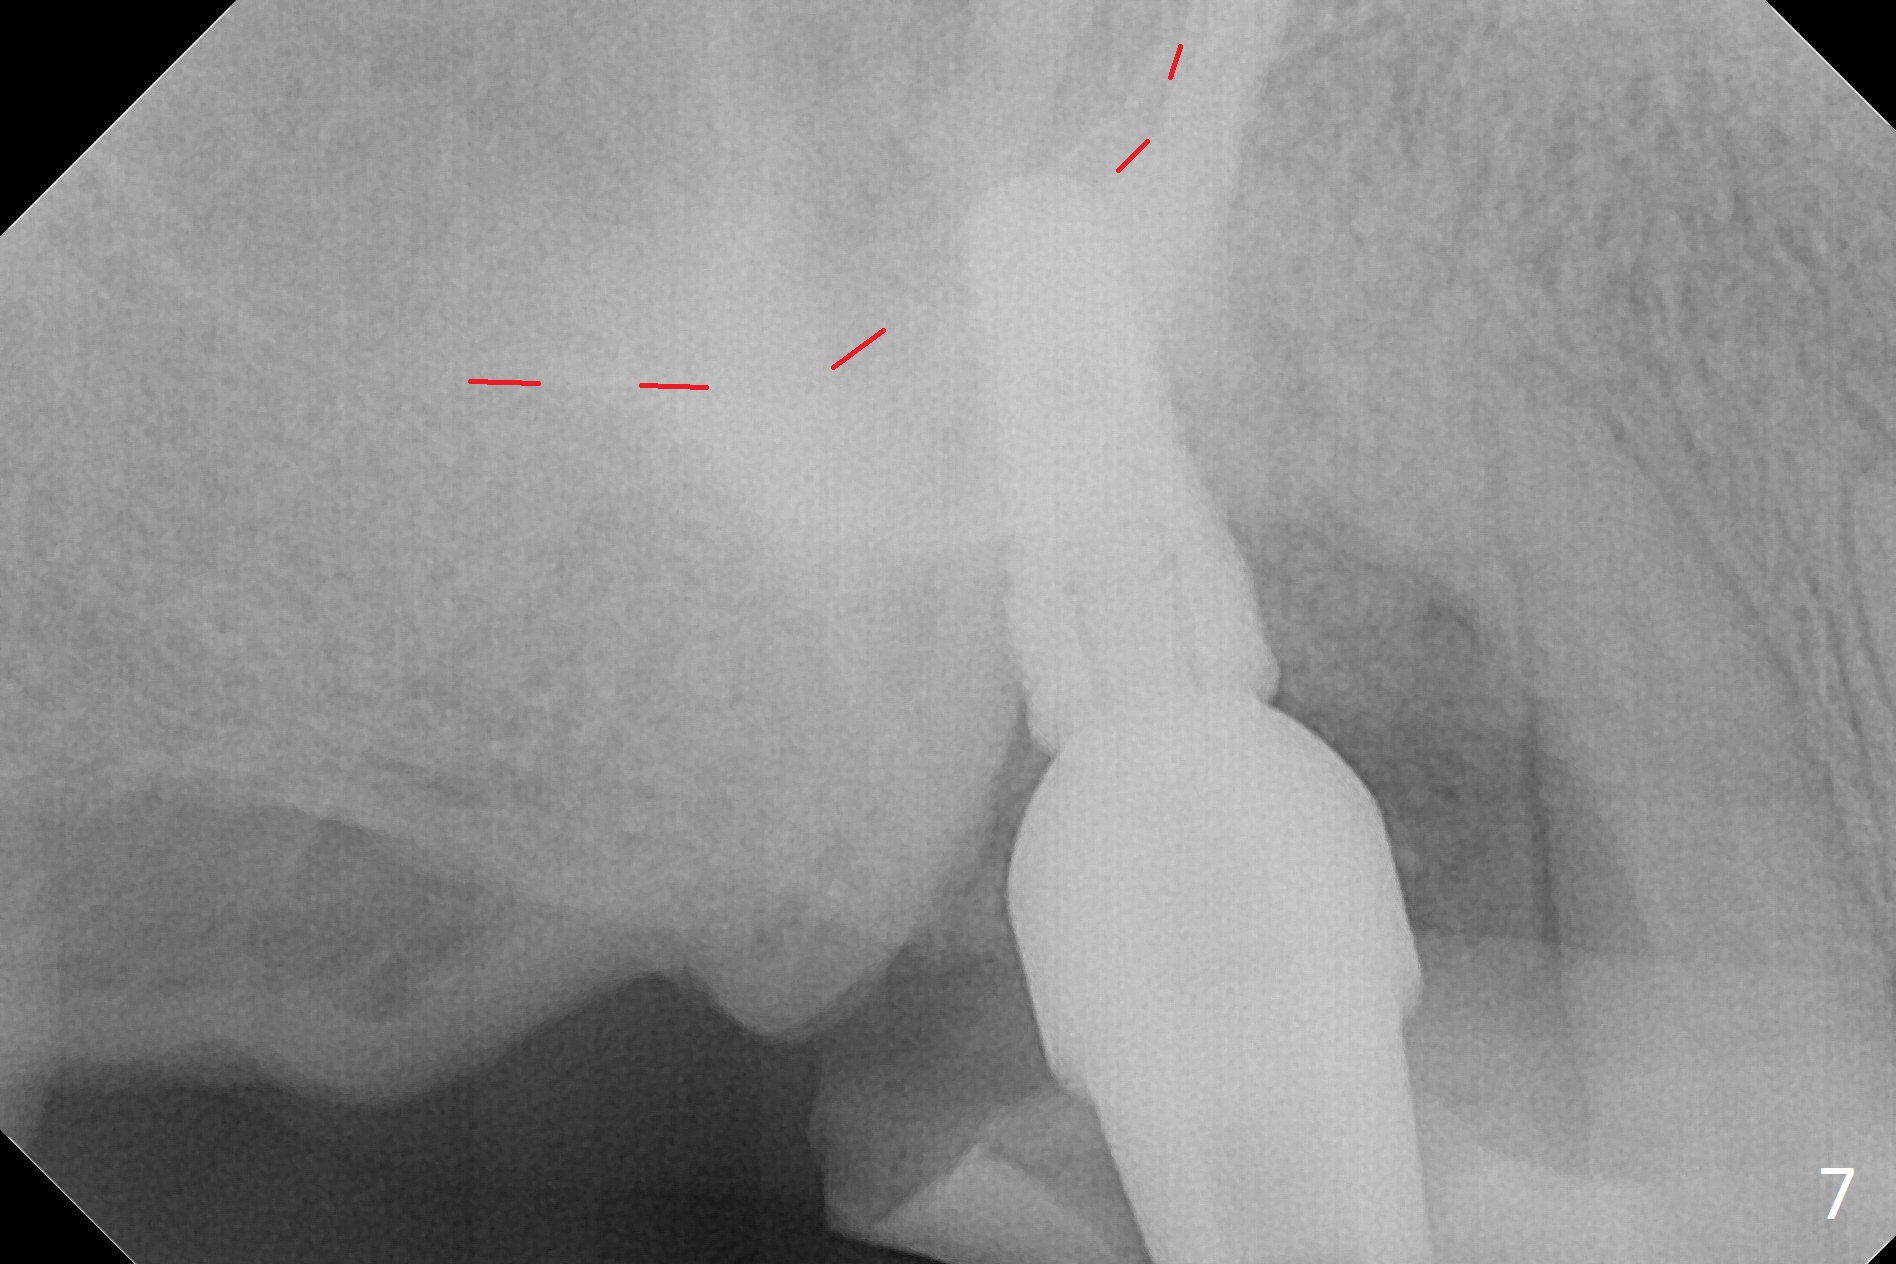

The palatal socket (Fig.1 P, packed with gauze) is intact, but implant trajectory may not be ideal. Buccal to the palatal socket are 2 pieces of the gingiva, buccal (B) and Septal (S). After the septal gingiva is pushed buccally (Fig.2 arrow), the underlying sloped septal bone is exposed (Fig.3 white area). Osteotomy is established as palatal as possible (Fig3 black circle) using DIO Sinus Master Kit, supplemented by Tatum osteotomes and DIO SM 3.8 mm tap drill for final sinus lift (Fig.4). Following further osteotomy using 4.1 and 4.5 mm taps, a 4.5x10 mm implant (Fig.6,7) with insertion torque >65 Ncm. Due to buccal bone loss, the coronal buccal threads are exposed 1-2 mm, which is covered by combination of allograft, autogenous bone and Osteogen. Prior to implantation, PRF plug and bone graft are used for sinus lift. The septal gingiva now is approximately 1-2 mm coronal to the implant plateau (Fig.5 S). The most coronal buccal gingival defect is covered by 3 pieces of PRF membrane (Fig.5 M) against a 6.8x5.5(6) mm abutment (A). Finally the socket is protected by periodontal dressing (Fig.8).